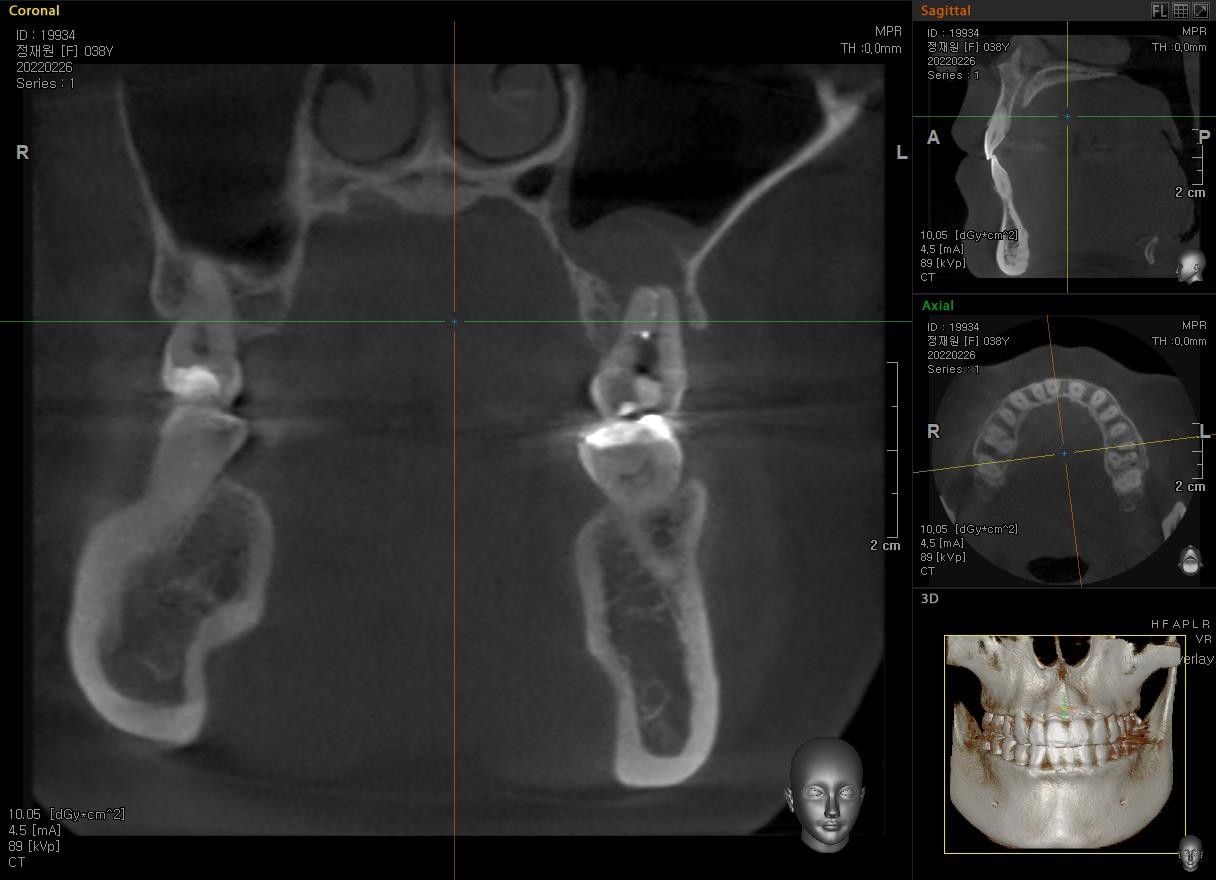

Case #1

치료 전